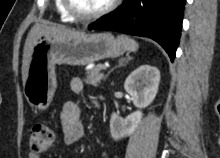

Современным высокоинформативным способом выявления патологических изменений поджелудочной железы является мультиспиральная компьютерная томография с прицельным сканированием органа. Метод КТ основан на применении рентгеновского излучения и способности органов и тканей поглощать рентгеновские лучи.

При необходимости детальной визуализации структуры железы, особенно в случае подозрения на развитие опухоли, назначается КТ поджелудочной железы с контрастом. Для этого применяются йодсодержащие контрастные препараты, которые вводятся пациенту внутривенно. Контрастное вещество, попадая в кровоток, контрастирует кровеносные сосуды и патологические очаги на фоне окружающих здоровых тканей.

Контрастирование позволяет отличить зоны воспаления, деструкции, разрастания фиброзной ткани и опухолевой трансформации от сохраненной паренхимы поджелудочной железы. КТ поджелудочной железы с контрастированием дает исчерпывающую информацию о состоянии органа и патологических процессах в нем.

При помощи специальных цифровых приложений данные, полученные при сканировании, преобразуются в трехмерные изображения органа, что дополнительно повышает точность и достоверность диагностики заболеваний поджелудочной железы.